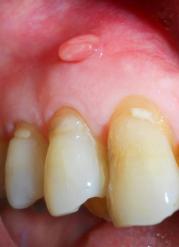

ხშირად კითხულობენ თუ რამდენად საშიშია ღრძილზე გაჩენილი ფისტულა. ეს შეკითხვა ბუნებრივია, რადგან ამ მდგომარეობას არ ახლავს რაიმე სიმპტომები, რაც მის “საშიშობაზე” შეიძლება მიუთითებდეს. არ ახლავს ტკივილი, შეშუპება, ანთებითი ცვლილებები ირგვლივ ქსოვილებში. ერთი სიტყვით, ისევე გამოიყურება, როგორც ღრძილზე გაჩენილი”მუწუკი”, რომელიც დაცლის შემდეგ თავისით ქრება. ასეთი უსიმპტომო მიმდინარეობის გამო ხშირად მას ყურადღებას არ აქცევენ და ასე გრძელდება წლების განმავლობაში. თუ გვეცოდინება რას წარმოადგენს ფისტულა, დავრწმუნდებით, რომ იგი საკმაოდ სერიოზული ნიშანია და ყურადღების მიქცევა აუცილებელია.

ფისტულა ღრძილზე წარმოადგენს ხვრელ-არხს, რომელიც აუცილებლად უკავშირდება ქსოვილის სიღრმეში არსებულ ჩირქოვან კერას. უმეტეს შემთხვევაში ეს ძვალში, კბილის ფესვის ირგვლივ განვითარებული აბსცესია (“პროცესი”, როგორც ხშირად უწოდებენ). ხვრელ-არხის გაჩენის შემთხვევაში ჩირქი პოულობს გზას და გარეთ გამოედინება. ასეთ შემთხვევაში ჩვეულებრივ, ადამიანი ყლაპავს ჩირქს, თანაც ეს ხდება ქრონულად, რაც თავისთავად ინფექციის ორგანიზმში გავრცელებას იწვევს. ჩირქოვანი კერის დაცლის შემდეგ ფისტულა იხურება, ზოგჯერ სრულიად უკვალოდ ქრება, შემდგომ გამწვავებამდე.